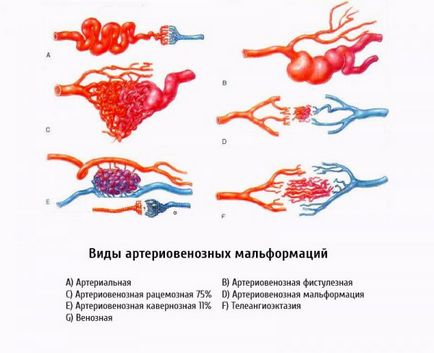

Arteriovenosus fejlődési rendellenesség okoz, tünetek és a kezelés

Arteriovenosus malformáció (AVM) egy komplex összefonódása abnormális artériák és vénák kapcsolódik egymáshoz útján egy vagy több vegyület az úgynevezett fisztulák vagy söntök. Ez összefonódása fejlődési hívják a kernel. Normális esetben, a vér az artériákban a rendszer nagy nyomás alatt. Aztán, ahogy a folyosón keresztül a kapilláris-ágyon a vénás rendszer, van egy lassú vérnyomásesést. Amikor AVM kapilláris ágy nem áll rendelkezésre, a vér az artériákban a vénákban közvetlenül belép a rendszerbe.